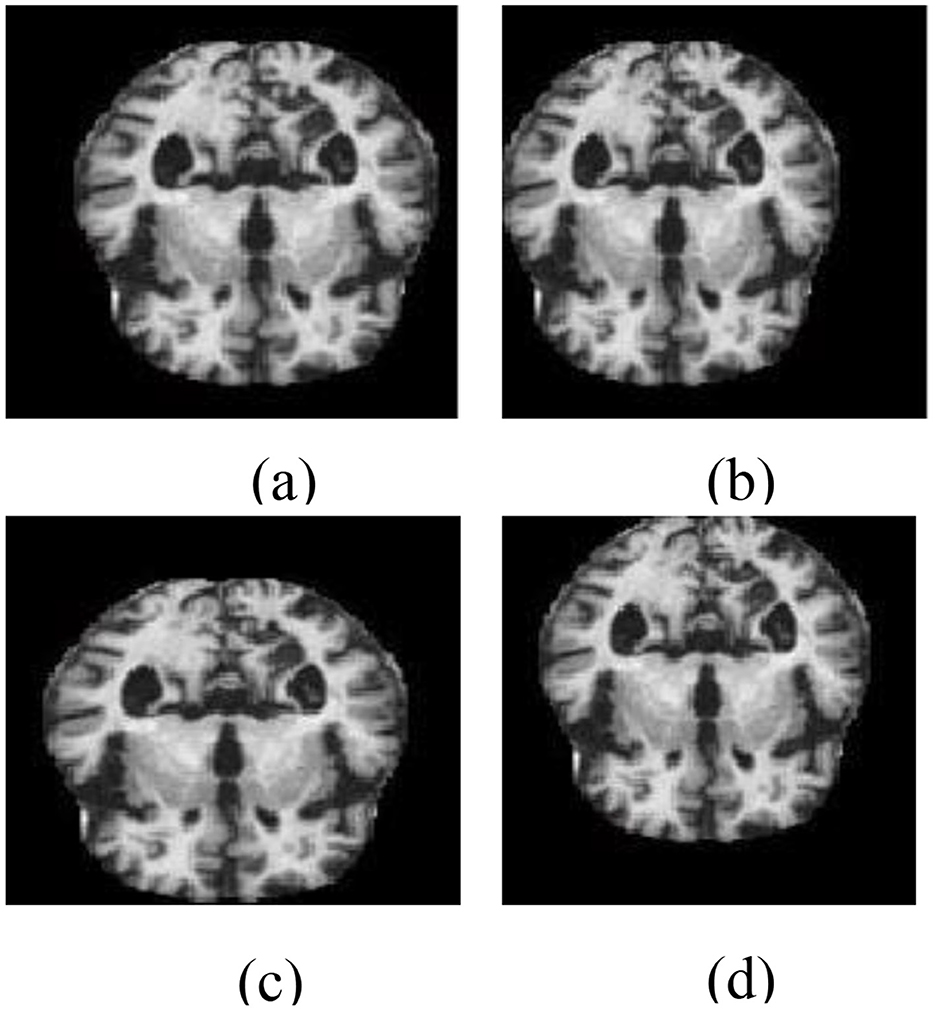

As part of the training pipeline, data augmentation was employed by applying directional translations to the input images, including shifts to the right, left, upward, and downward (Li et al., 2018), to increase dataset diversity and mitigate overfitting. Directional transformations were chosen because of their ability to maintain the anatomical integrity of brain areas while introducing spatial variation. Unlike other augmentation methods, such as random rotations, elastic deformations, or intensity-based modifications, directional translations preserve the alignment and structural consistency required for reliable AD classification using structural MRI. This method keeps the enhanced data clinically relevant while improving the model's robustness, generalization capability, and functional efficiency during training. The data-augmented images are shown in Figure 4.

Figure 4. Data augmentation outputs illustrating directional transformations: (a) left-shifted image, (b) right-shifted image, (c) upward-shifted image, and (d) downward-shifted image. These augmented images are created to improve diversity during the training phase.